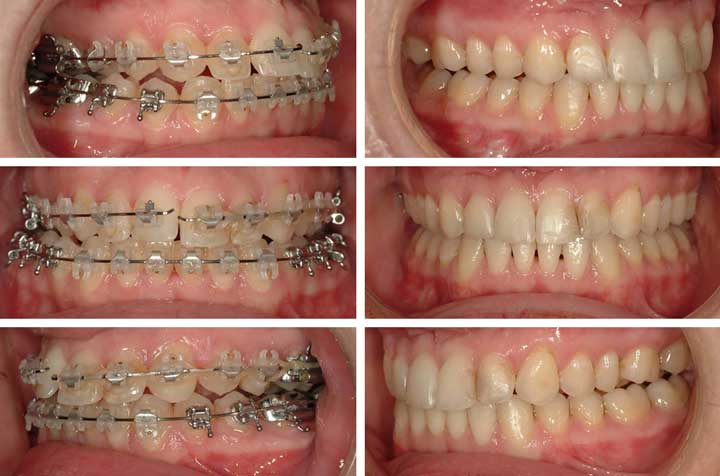

Before & After

Case Gallery

Review 50 real patient cases — including corrective jaw surgery, dental implants, and facial cosmetic procedures performed by Dr. Antipov.

Case 1

Corrective Jaw Surgery • Case 1 • 4 photos